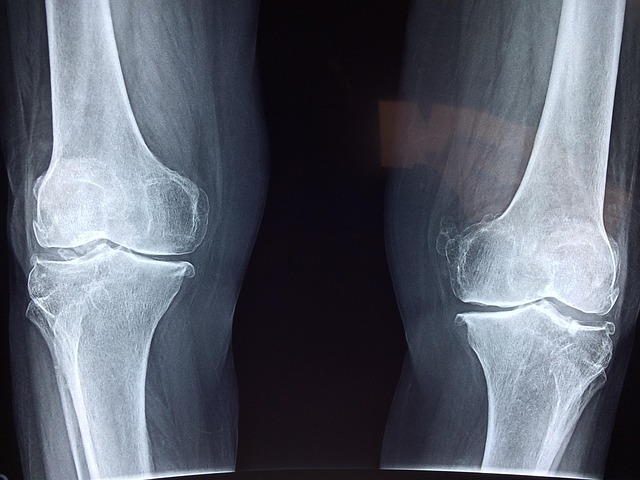

골다공증이란?

골다공증은 뼈 밀도가 낮아지고 약해져 쉽게 부러지는 상태를 말합니다. 이는 나이가 들면서 자연스럽게 발생할 수 있지만, 특히 폐경 후 여성들에게 흔히 나타나는 질환입니다.

주요 원인으로는 나이 증가, 호르몬 변화, 영양 부족, 운동 부족 등이 있습니다. 골다공증은 뼈의 강도가 약해져 골절 위험을 크게 증가시키며, 초기에는 뚜렷한 증상이 없지만 시간이 지나면서 키가 줄어들거나 허리 통증이 발생하고, 작은 충격에도 쉽게 뼈가 부러질 수 있습니다.